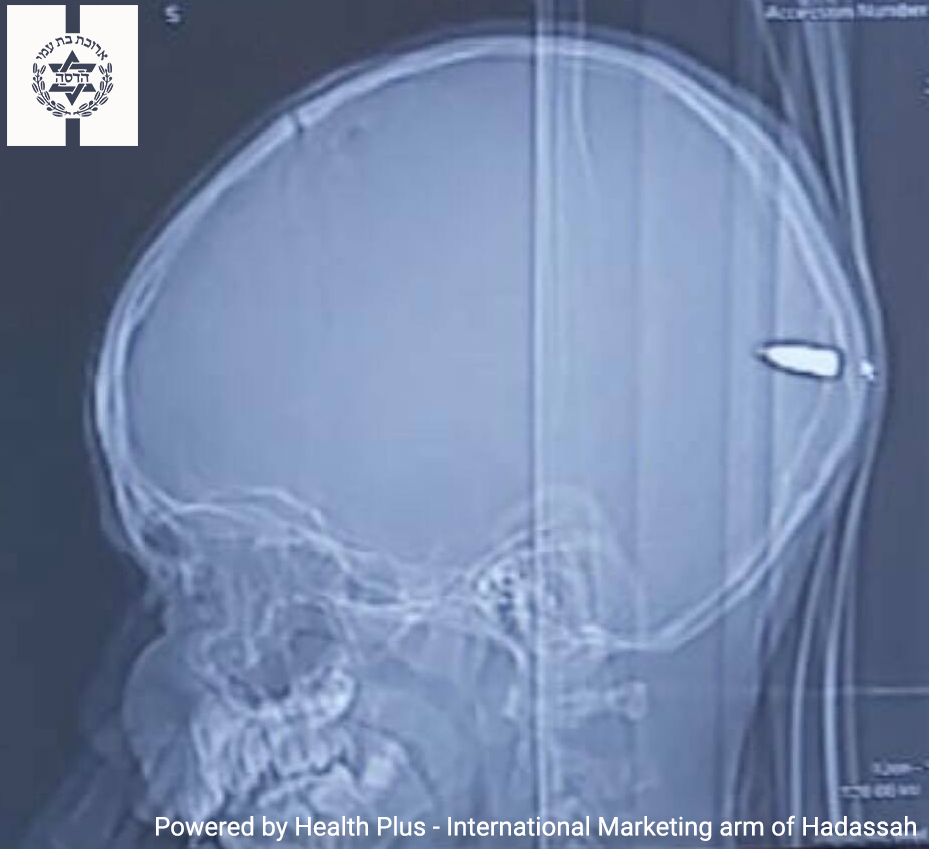

В клинике “Хадасса” вылечили 9-летнего мальчика после огнестрельного ранения в голову

Случайное огнестрельное ранение в голову чуть не унесло жизнь 9-летнего мальчика. После происшествия ребенок был экстренно доставлен в клинику “Хадасса”, где ему сделали компьютерную томографию. На снимке было видно, что ¾-дюймовая пуля пробила правую сторону черепа, прошла через мозг и застряла в левой части головы маленького пациента. Однако во время операции пуля оказалась не в том месте, где ее искали хирурги. “Мы перевернули мальчика на живот, чтобы получить оптимальный доступ к левой части его головы. Вероятно, из-за силы тяжести пуля сместилась”, - объясняет старший детский нейрохирург доктор Гай Элор. С помощью ультразвукового и рентгеновского исследования хирургическая бригада обнаружила, что пуля вошла на несколько сантиметров в мозг ребенка и имплантировалась в зрительную кору. Данная часть мозга отвечает за моторику, поведение и мышление человека. Как только пуля была обнаружена, хирурги аккуратно извлекли ее с помощью штыкового пинцета. Анестезиолог Хлоя Мимуни подчеркнул

Случайное огнестрельное ранение в голову чуть не унесло жизнь 9-летнего мальчика. После происшествия ребенок был экстренно доставлен в клинику “Хадасса”, где ему сделали компьютерную томографию. На снимке было видно, что ¾-дюймовая пуля пробила правую сторону черепа, прошла через мозг и застряла в левой части головы маленького пациента. Однако во время операции пуля оказалась не в том месте, где ее искали хирурги.

“Мы перевернули мальчика на живот, чтобы получить оптимальный доступ к левой части его головы. Вероятно, из-за силы тяжести пуля сместилась”, - объясняет старший детский нейрохирург доктор Гай Элор.

С помощью ультразвукового и рентгеновского исследования хирургическая бригада обнаружила, что пуля вошла на несколько сантиметров в мозг ребенка и имплантировалась в зрительную кору. Данная часть мозга отвечает за моторику, поведение и мышление человека. Как только пуля была обнаружена, хирурги аккуратно извлекли ее с помощью штыкового пинцета.